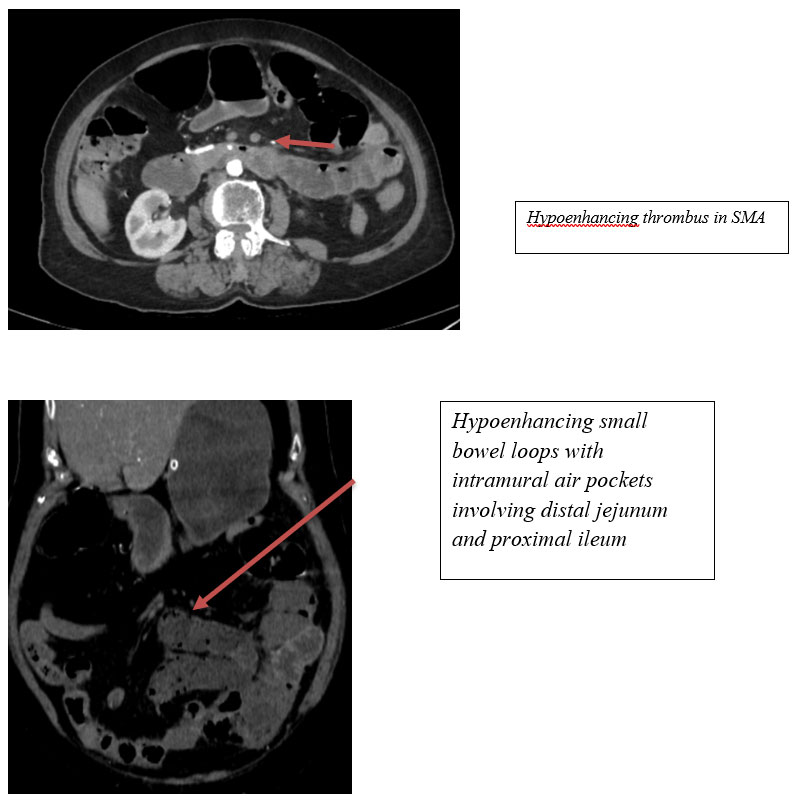

CECT Findings:

– Near‑complete occlusion of distal main trunk of the superior mesenteric artery (SMA).

– Hypoenhancing small bowel loops with intramural air pockets involving distal jejunum and proximal ileum — likely ischemic bowel.

– Distal ileal loops dilated with intraluminal air pockets — possible ileus.

Acute mesenteric ischemia is a critical diagnosis requiring prompt recognition. Elderly patients, particularly those with vascular risk factors, are vulnerable to SMA occlusion. Radiological findings such as hypoenhancing bowel, pneumatosis intestinalis, bowel dilatation, and vascular cutoff are key indicators of bowel ischemia. Early surgical intervention or endovascular management can significantly improve outcomes. This case underscores the role of CECT in detecting life‑threatening ischemia even in the absence of overt pneumoperitoneum.

Superior mesenteric artery occlusion leads to compromised perfusion of midgut structures. In elderly patients, thromboembolic disease is a common cause. CT features of established ischemia include poor bowel wall enhancement, intramural air, mesenteric fat stranding, and portal venous gas. Differentiating viable from non‑viable bowel is essential for guiding emergency management. Immediate revascularization and surgical assessment are crucial in preventing bowel infarction.